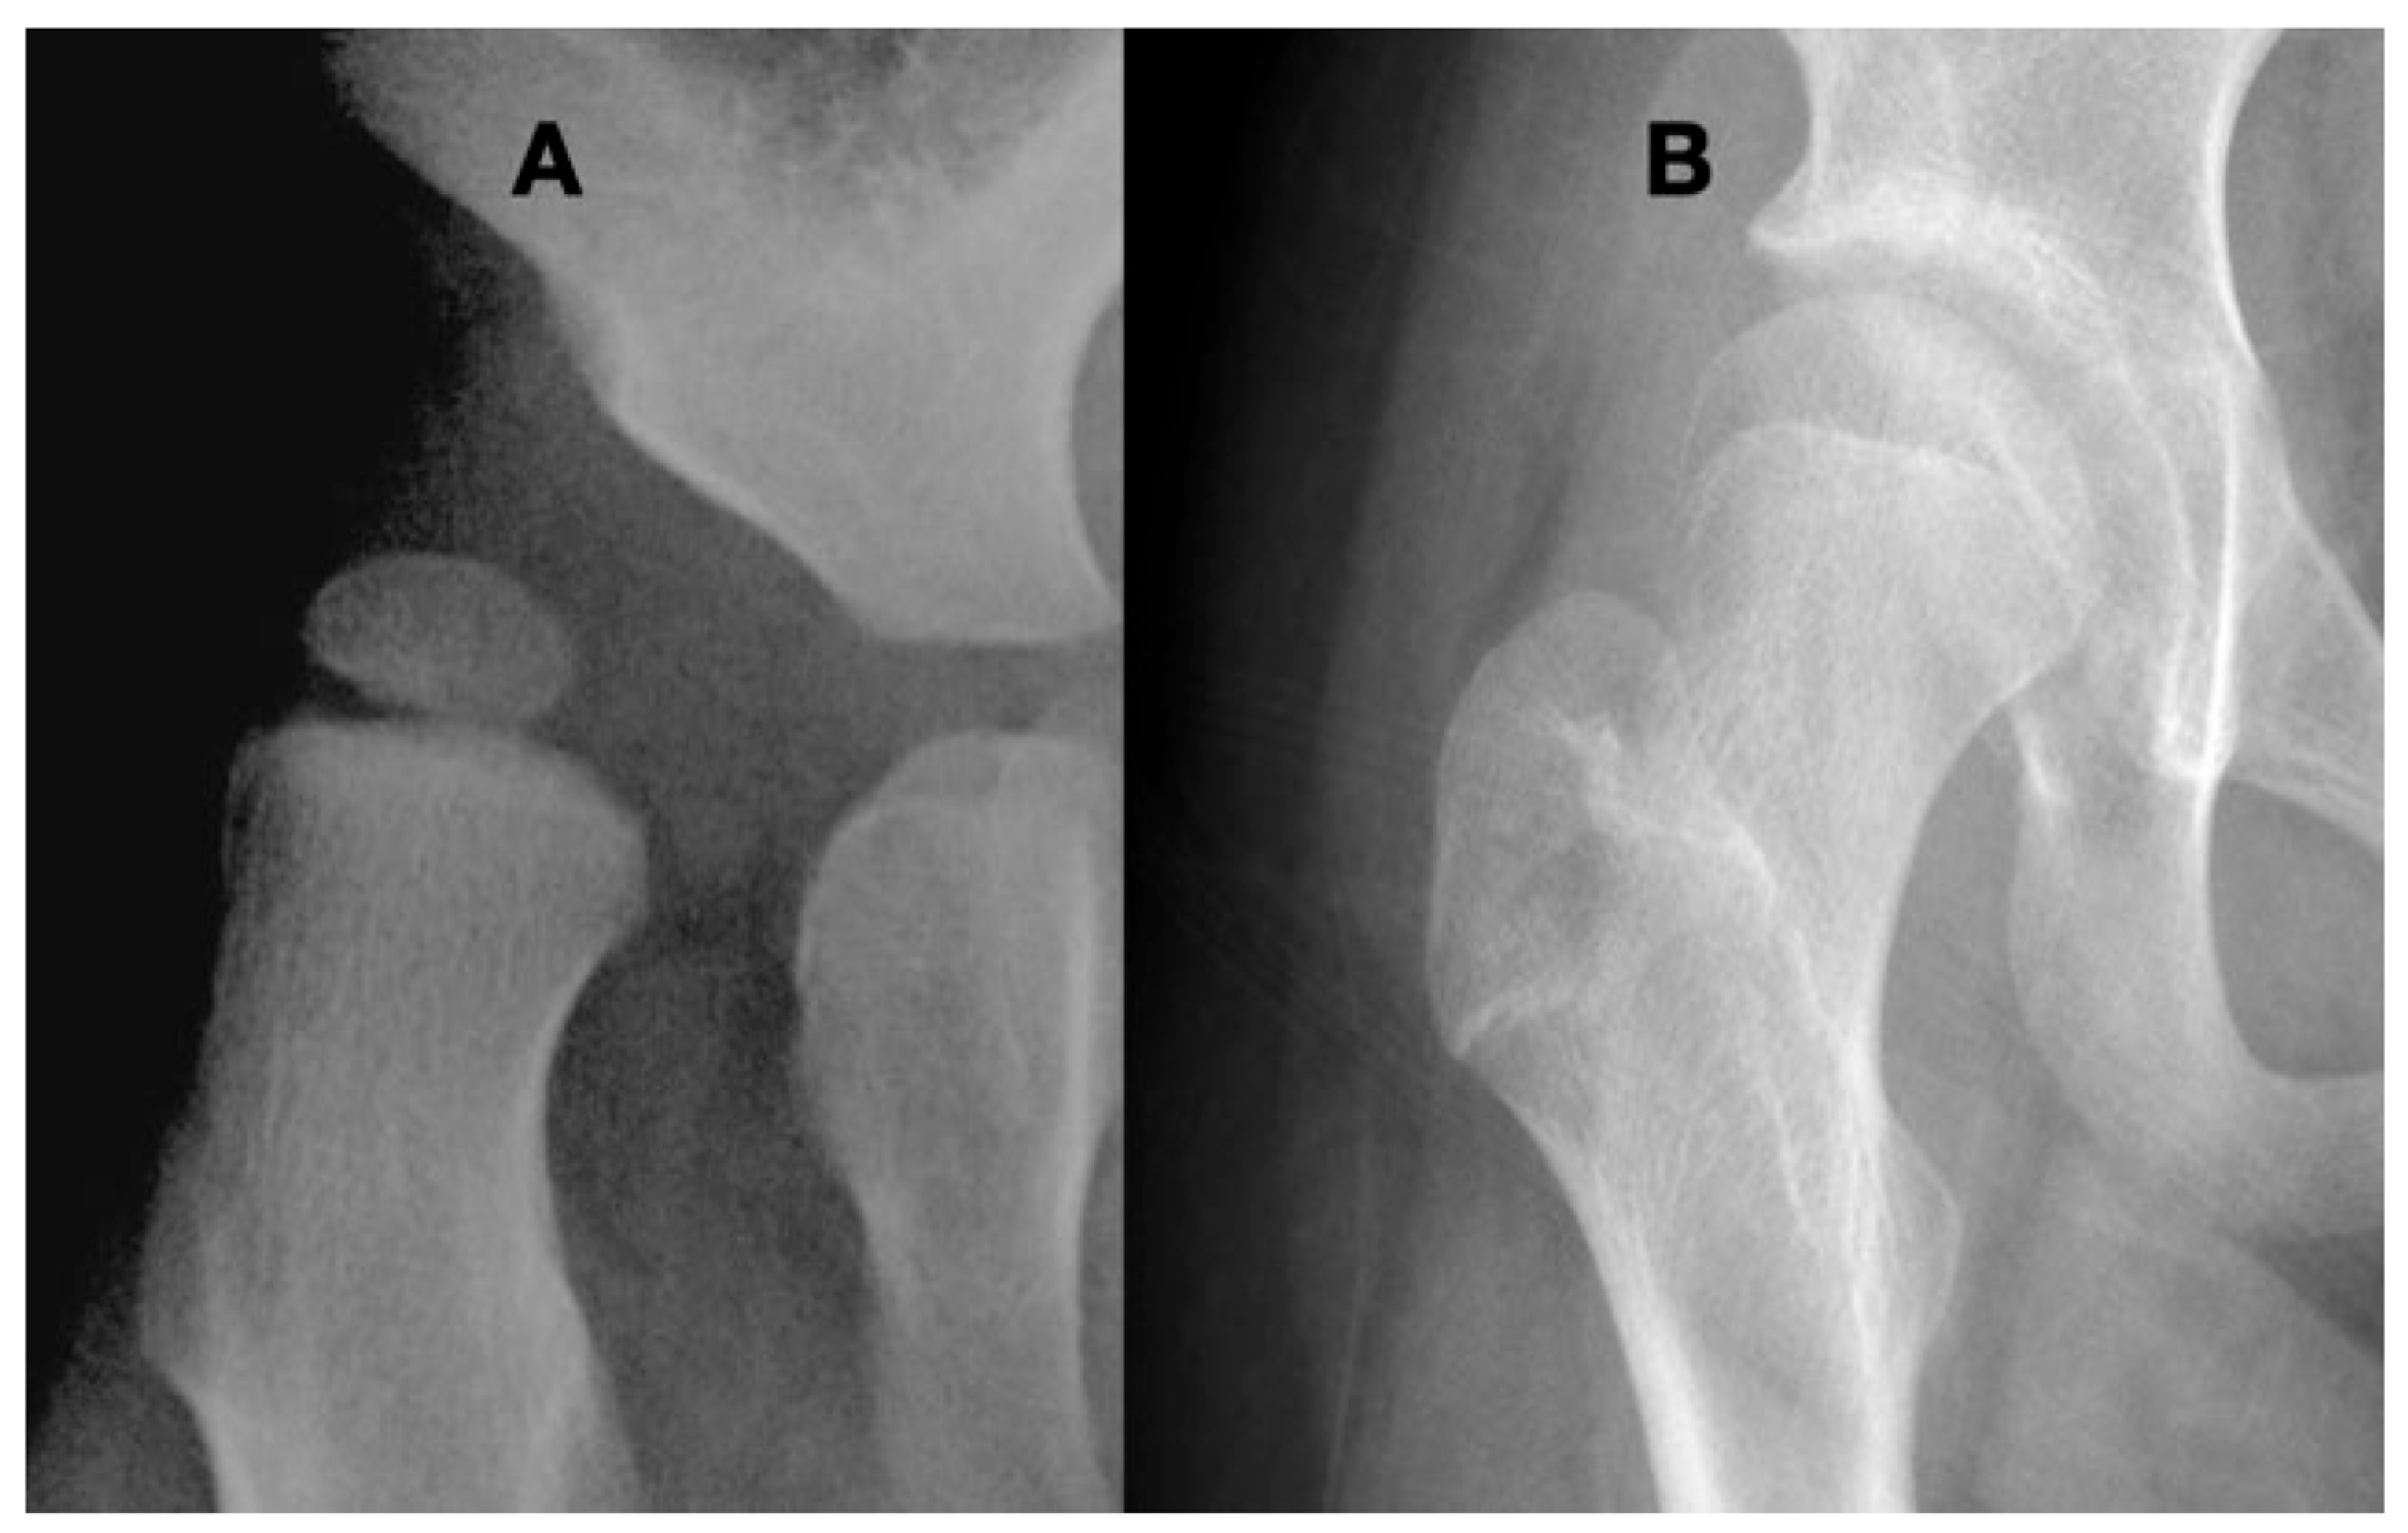

3.3.1. Impact of Abnormal Motor Function on Hip Development in Ambulatory Children

3.3.2. Pathology of Hip Development in Nonambulatory Children

3.3.3. Pathology of Hip Development in Children with Low Tone and Muscle Weakness